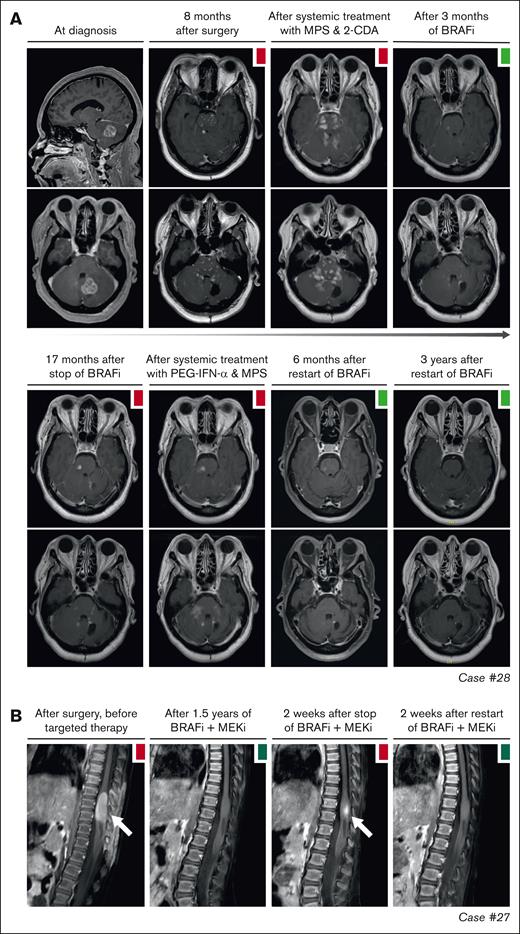

Objective responses were generally durable, although there were instances of PD in 11 of 27 (41%) patients (Figure 2). In 10 of 11 patients, these instances were related to a dose reduction or therapy interruption. Responses were recaptured in 9 of 10 cases after the dose was increased or therapy was restarted. For example, case 17 with ECD had increased fluorodeoxyglucose uptake in a left acetabular lesion after intermittent dosing of dabrafenib/trametinib (week on/week off; initiated as exit strategy after 3 years of treatment). After returning to continuous therapy, fluorodeoxyglucose uptake in the acetabular lesion decreased again (Figure 3B). Similarly, in case 36 with CNS-RDD (Figure 3C) and cases 27 and 28 with CNS-XG (Figure 4), disease progression was observed on MRI after dose reduction or stop of targeted therapy. In all 3 cases, objective responses were recaptured after dose escalation or restart of therapy (Figure 2). Potential acquired resistance to targeted therapy was only observed in case 16 with ECD, who had progression of a single lung nodule despite adequate intake and dosing of dabrafenib (150 mg twice daily). No biopsy of the nodule was taken. The patient subsequently switched to trametinib, which resulted in a PR at the end of follow-up (Figure 3D).

Disease progression after targeted therapy interruption. (A) Sagittal and axial MRI images of case 28, with CNS-AXG showing response of brain lesions to conventional therapies and targeted treatment with vemurafenib. After an initial PR to vemurafenib, targeted treatment was interrupted because of discontinued insurance coverage. Hereafter, brain lesions slowly progressed. Vemurafenib was restarted 3.6 years after interruption and quickly resulted in a decrease of brain lesions, with almost no lesions discernible at last follow-up. (B) Sagittal MRI images of case 27, with CNS-JXG showing relapse of a contrast-enhanced intramedullary spinal cord tumor after targeted therapy interruption. In this young child, treatment with dabrafenib and trametinib was interrupted after 1.6 years of therapy, while in complete radiologic remission. As an exit strategy, trametinib was stopped first, followed by dabrafenib 2 weeks later. MRI after stop of trametinib revealed persistent radiologic CR. However, MRI 2 weeks after stop of dabrafenib revealed recurrence of contrast-enhancement, consistent with a relapse of disease. MRI 2 weeks after restart of dabrafenib and trametinib showed that the radiologic response was recaptured. JXG, juvenile XG; MPS, methylprednisolone.